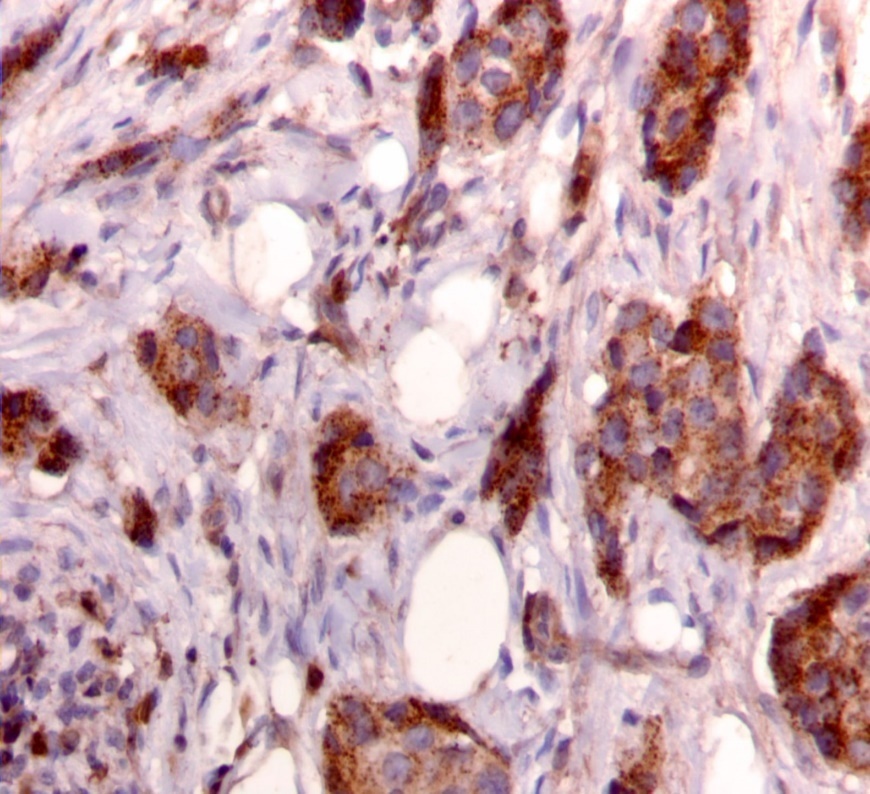

Figure 2.Diffuse cytoplasmic staining pattern for IRS-2. (IRS-2 immunohistochemical stain, 200x magnification)

Diffuse cytoplasmic staining pattern for IRS-2. (IRS-2 immunohistochemical stain, 200x magnification)

We used the following histologic criteria for IRS-1 and IRS-2 staining patterns which are outlined in a previous study.13 For IRS-1, a nuclear pattern was defined as diffuse nuclear staining (Figure 1). IRS-2 staining patterns were defined using the following criteria: Diffuse cytoplasmic staining was defined as evenly distributed cytoplasmic reactivity (Figure 2); punctate cytoplasmic staining was defined as clearly demarcated puncta of staining within the cytoplasm (Figure 3); and membrane staining was defined as focal or diffuse membranous staining (Figure 4). Sections of normal pancreas and normal breast tissue were used for positive and negative controls. The pathologists assessing staining patterns were blinded to the tumor recurrence score and all other data at the time of assessment.